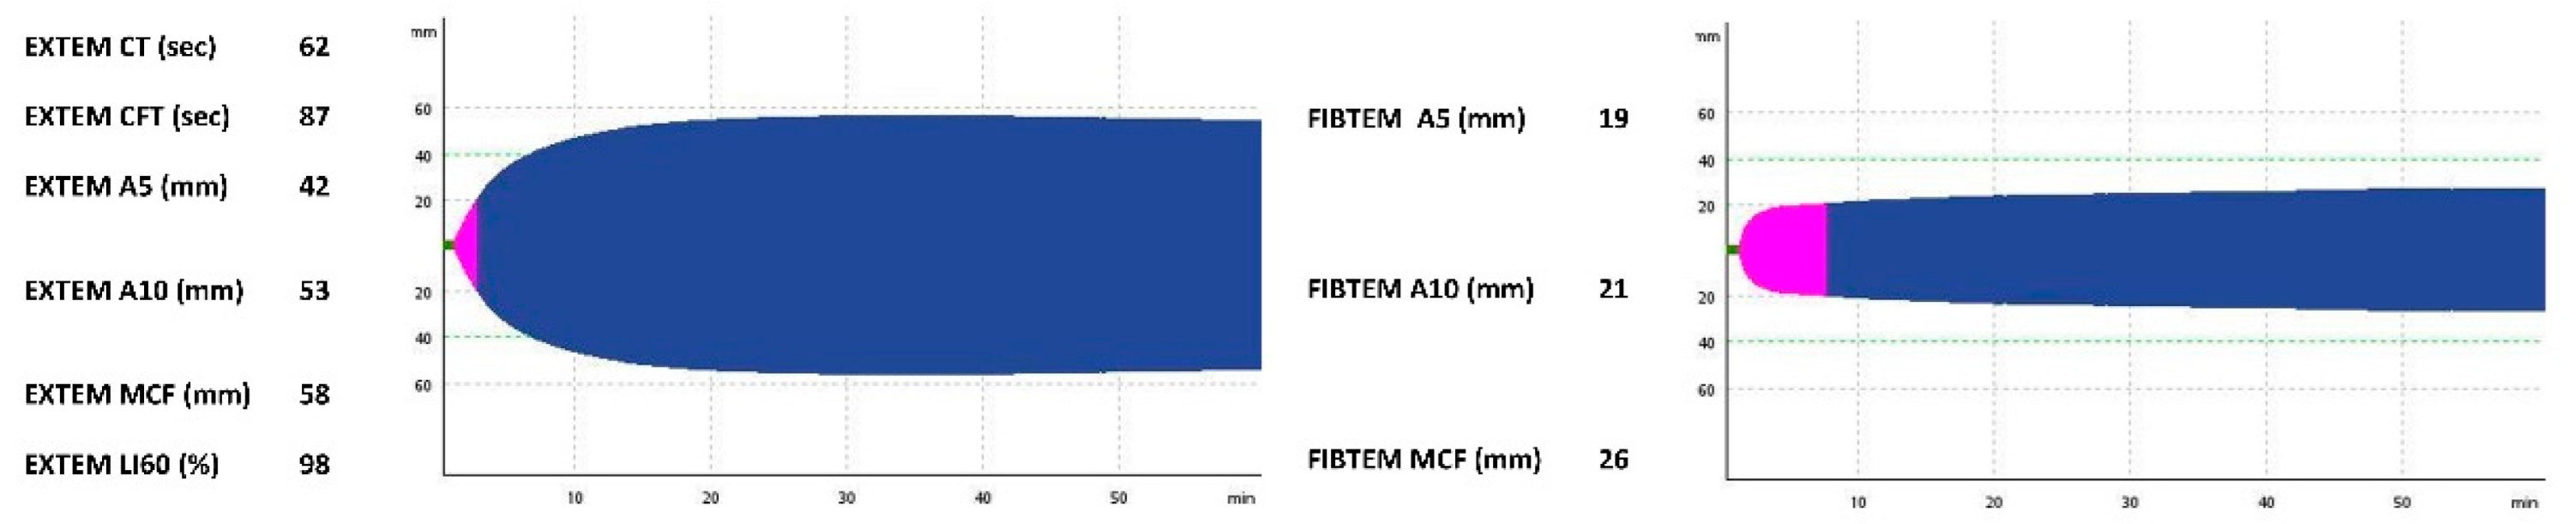

| EXTEM CT (s) | N/A | 128 | 54 | 163 | N/A | 62 |

| EXTEM CFT (s) | N/A | 277 | 190 | 650 | N/A | 87 |

| EXTEM A5 (mm) | N/A | 21 | 26 | 12 | N/A | 42 |

| EXTEM A10 (mm) | N/A | 29 | 37 | 19 | N/A | 53 |

| EXTEM MCF (mm) | N/A | 38 | 48 | 32 | N/A | 58 |

| EXTEM LI60 (%) | N/A | 100 | 100 | 100 | N/A | 98 |

| FIBTEM A5 (mm) | N/A | 5 | 13 | 4 | N/A | 19 |

| FIBTEM A10 (mm) | N/A | 6 | 15 | 4 | N/A | 21 |

| FIBTEM MCF (mm) | N/A | 6 | 20 | 4 | N/A | 26 |